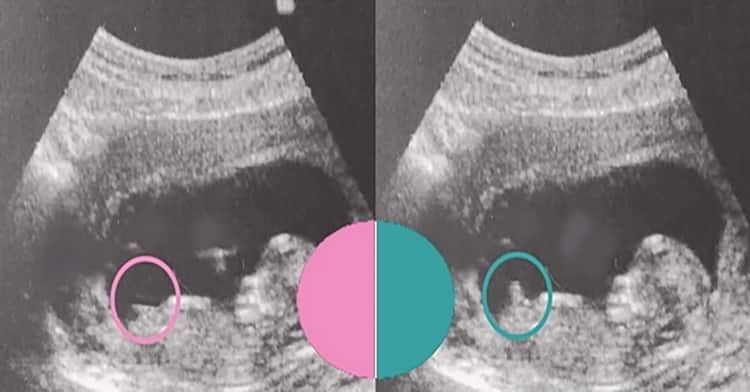

УЗИ на 12 неделе . Некоторые эксперты ,как-то по бугорку определяют пол , мы смотрим и выглядываем ,не можем ничего понять😄

Если это бугорок, то на девочку похоже, форма головы тоже девочки. У мальчиков говорят лоб более выпирает